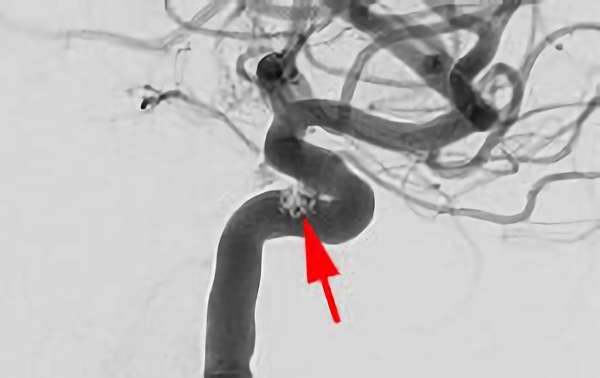

'26年4月

左椎骨動脈後下小脳動脈分岐部動脈瘤

70代

院内外来

No.1628 手術前

No.1628 手術中

No.1628 手術後